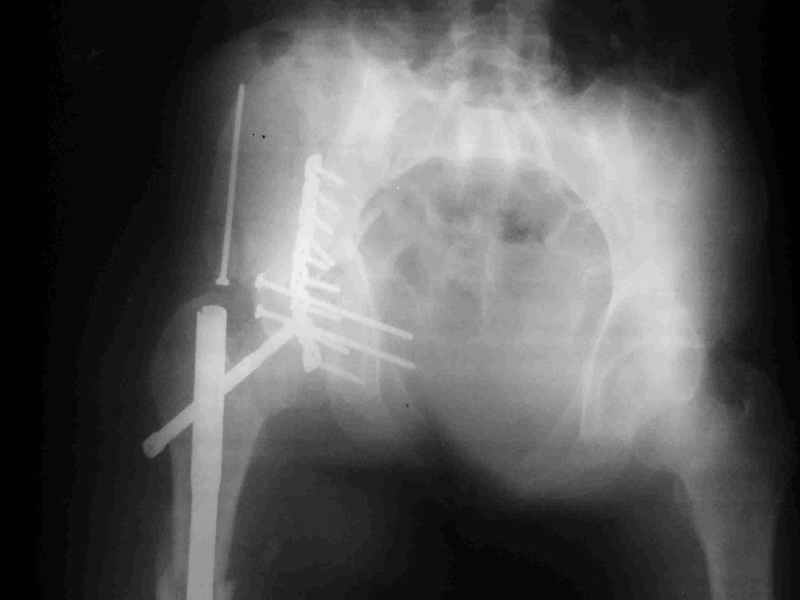

перелом крыла правой подвздошной кости, перелом обеих колонн вертлужной впадины, двусторонний перелом лонных костей (С2.2) повреждение передних связок правого крестцово-подвздошного сочленения,

ипсилатеральный перелом шейки и диафиза бедра.

К сожалению, набора для ретроградного или антеградного реконструктивного штифтования в операционной нет, поэтому доставка заняла н-ное время. Вопрос, который возник у меня- по поводу оптимальной тактики хирургии: вся фиксация в один этап из расширенного доступа или последовательно сначала бедро и позже реконструкция впадины, комбинированный доступ к впадине отдельно к передней и задней колоннам или из расширенного илеофеморального одного доступа. Все-таки решил остановиться на одноэтапном подходе и спустя 5 дней (как раз и наборы привезли) из расширенного илеофеморального доступа сначала фиксировал реконструктивным штифтом Smith&Nephews бедро и

шейку (благо перелом шейки 2 типа -относительно стабильный) затем фрагмент крыла подвздошной кости Lag screw, далее пластина на заднюю колонну и винты в переднюю колонну.(с размерами и направлением винтов ошибка вышла:-((, но интраоперационно у меня была полная уверенность , что винты *ушли* в лонную кость).

Еще раз спасибо за комментарии и готовность помочь с имплантами. Постоп картинки в приложении,